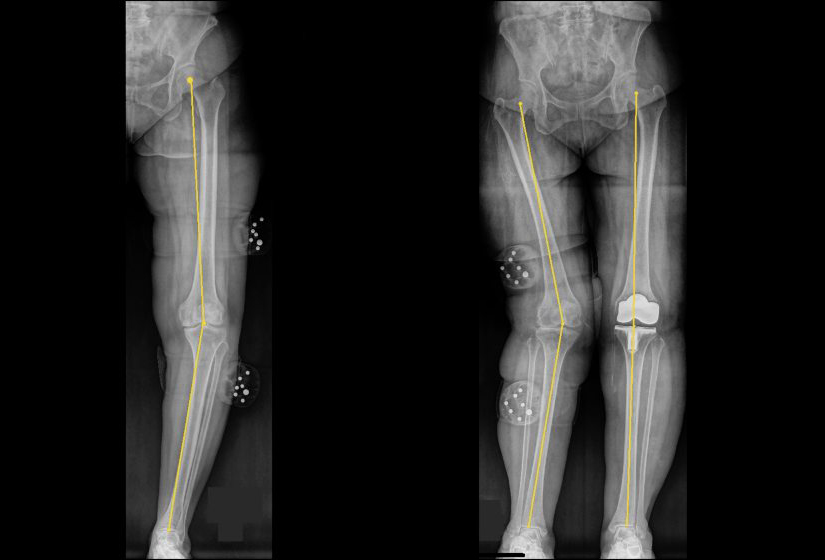

“O型腿又叫做‘膝内翻’,指的是膝盖往外凸出、小腿向内弯,看起来就像一个‘O’字。最直接的诊断方式是拍X光片。医生会从髋关节画一条直线到脚的中心。正常情况下,这条线会依序经过髂前上棘、膝盖中心和脚的正中点,呈现180度的直线。但如果是O型腿,这条力线就会偏向膝盖内侧,这种情况称为‘力线内移’。

此外,向内偏移被称为O型腿,向外偏移则被称为X型腿,后者是双膝并拢时脚踝分开,腿呈‘X’形。

X型腿X光图(右图):患者的左腿结构患有X型腿。这种力线分布容易使膝关节外侧软骨磨损,长期下来可能发展为退化性关节炎。